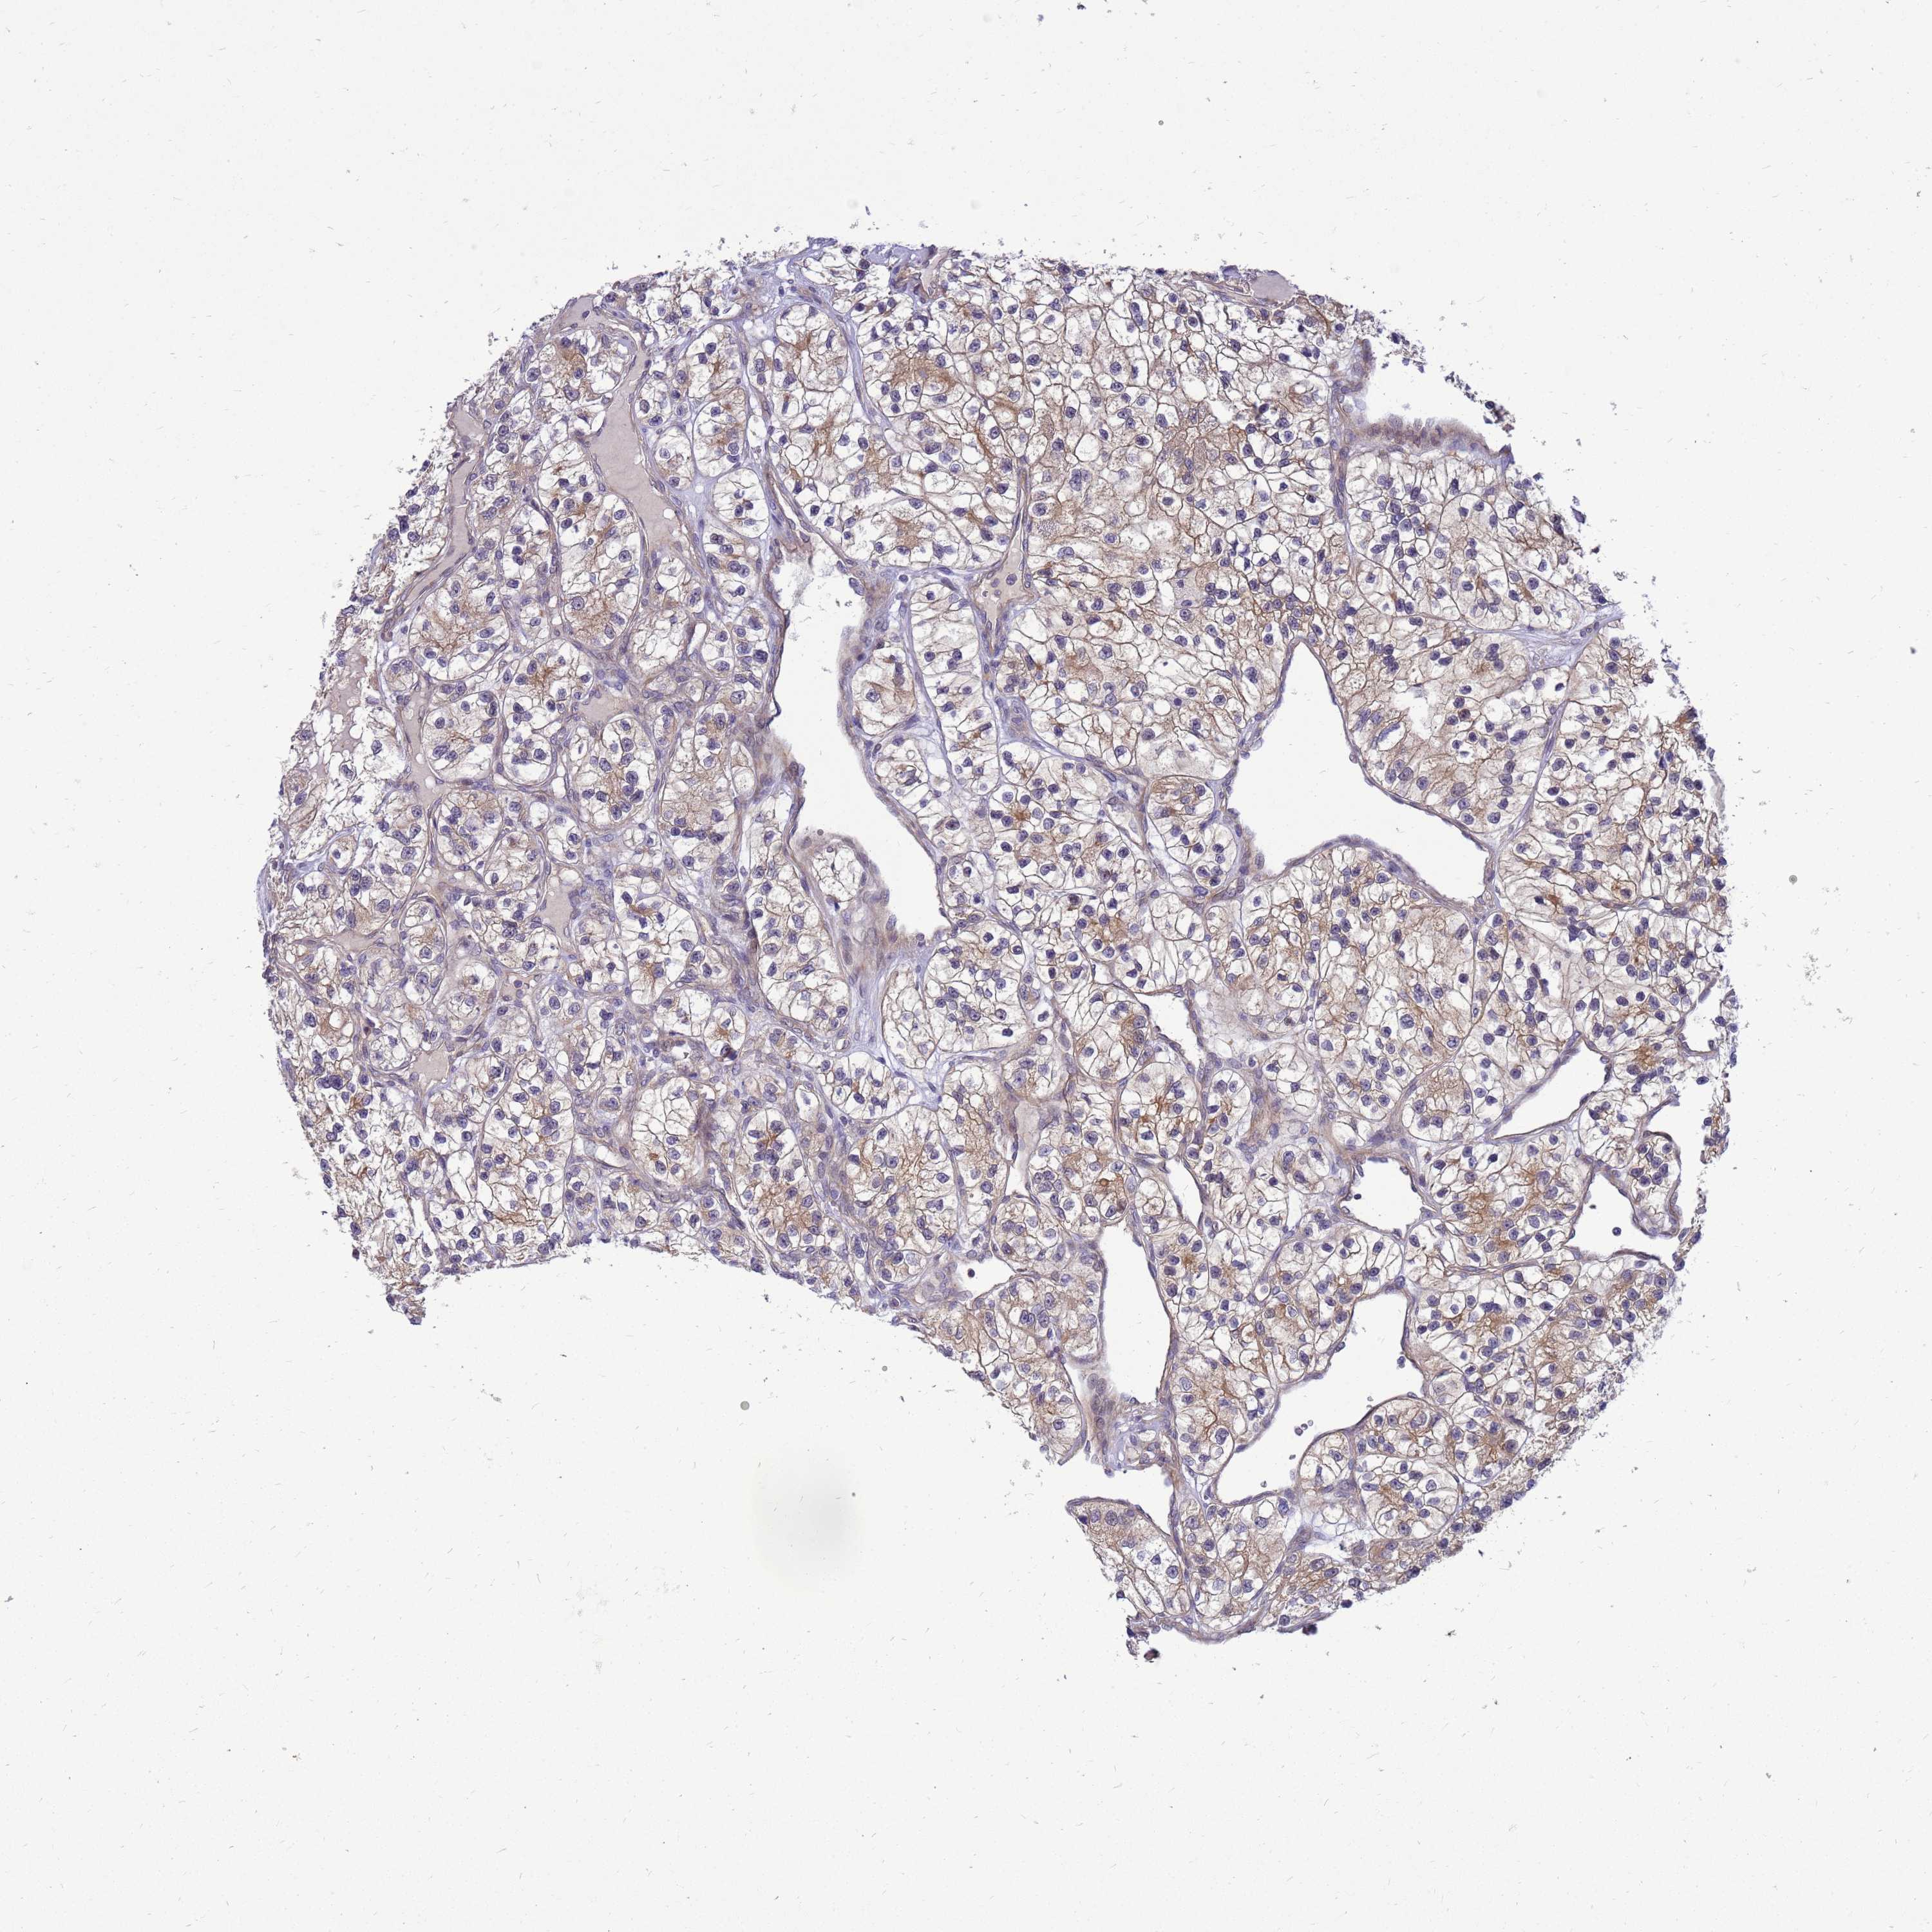

KIDNEY RENAL PAPILLARY CELL CARCINOMA (TCGA) - Interactive survival scatter ploti

ENOPH1 is not prognostic in Kidney Renal Papillary Cell Carcinoma (TCGA)